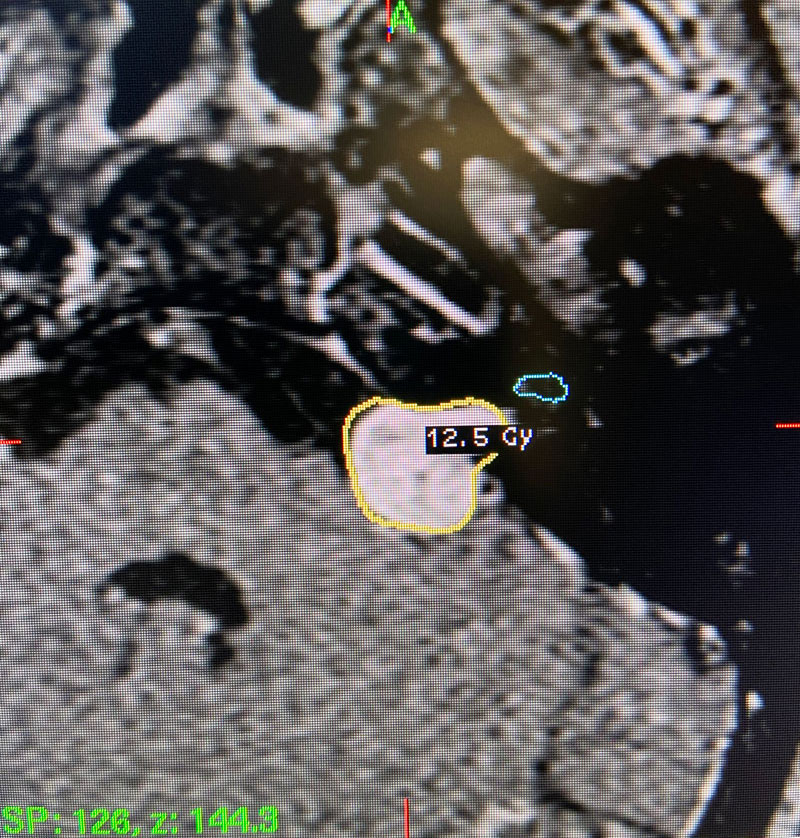

Image 2: Intra-operative Gamma Knife treatment planning for the left acoustic neuroma. A tightly conformal treatment is set for 12.5Gy to the 50% isodose line. The cochlea has also been contoured, based off a fused image from a fine cut T2 sequence.

Technical Aspects of Gamma Knife Treatment: Dose to the tumor is set to 12-13 Gy to the edge of the tumor. The 50% isodose line is set to the edge of the tumor. Dosing under 12Gy is less effective at tumor control, and dosing over 13Gy puts the facial nerve at risk. There is evidence that the radiation dose to the cochlea affects whether hearing will ultimately be preserved. As such, if there is meaningful hearing at the time of treatment, the mean cochlear dose should be set to 4.2Gy or less. The cochlea is separately contoured at the time of treatment off fine cut T2 sequences which are then fused to the post contrast T1 images.

This patient: This patient had a moderate sized , symptomatic acoustic neuroma with serviceable hearing. Gamma Knife was recommended. A Gamma Knife treatment was performed by Dr. Michael Brisman. The radiation oncologist was Dr. Leester Wu. A treatment plan was made that was very conformal to the tumor. A prescription of 12.5Gy to the 50% isodose line was delivered. This plan involved a mean cochlear dose of 3.5Gy.